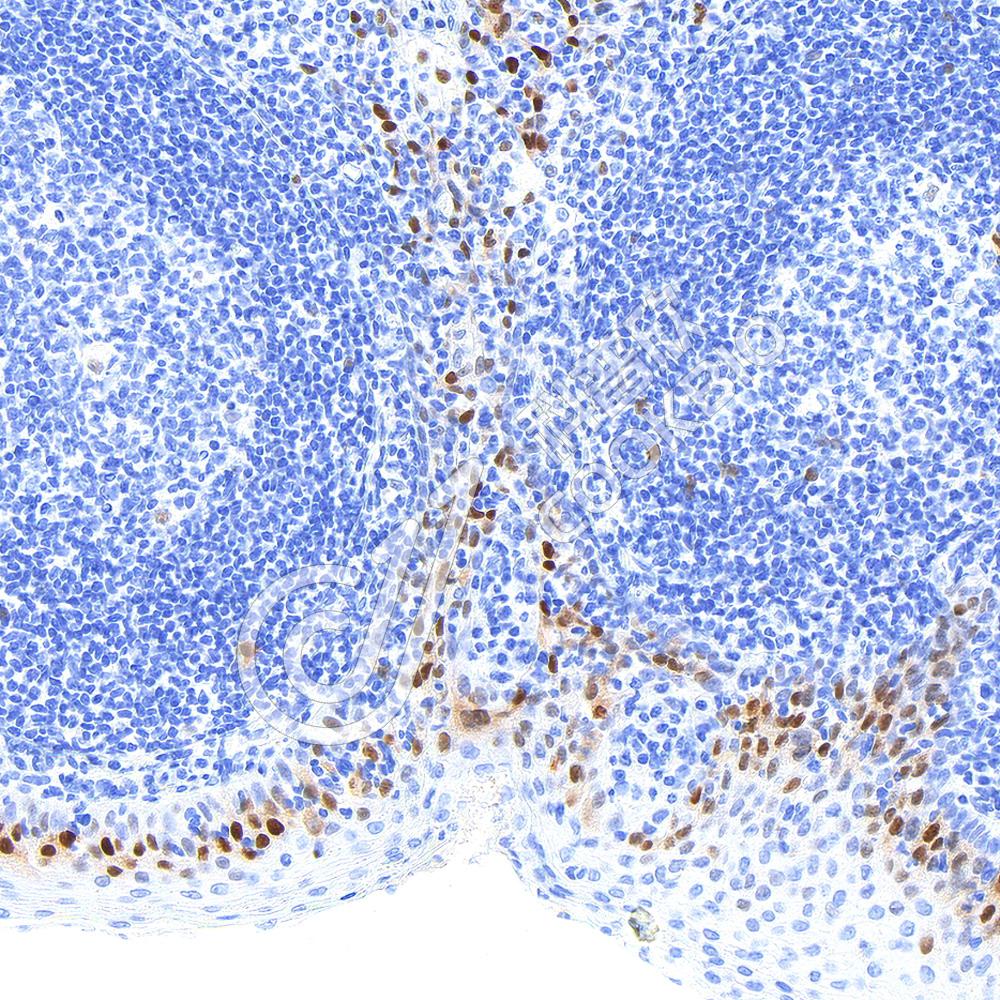

IHC检测Cyclin D1蛋白(货号 K5454116).

样品: 人扁桃体, 4%多聚甲醛 (货号KSG1101) 固定12-24小时.

抗原修复: Tris-EDTA抗原修复液(pH 9.0) (货号KSG1203), 高压锅均匀喷气计时2分钟.

—抗: 1: 1000稀释, 4℃ 孵育过夜.

二抗: S-vision免疫组化多聚二抗(山羊抗兔),即用型 (货号KB3906), 室温孵育20分钟.